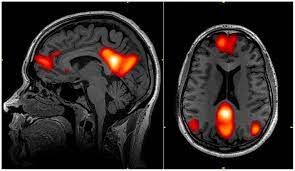

default mode network

The DMN is a set of brain regions and pathways that exhibits strong low-frequency oscillations — i.e. activity — during resting state and is thought to be activated when individuals are focused on their internal mental-state processes such as self-referential processing, introspection, autobiographical memory retrieval, and imagining the future.

fMRI of the Default Mode Network

Psychedelics are possibly the most immediate and profound way to reduce the control of the DMN over the mind. Neuro-imaging studies have consistently shown that psychedelics like LSD and psilocybin significantly reduce DMN connectivity.